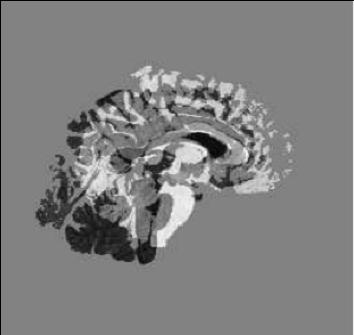

| our model | ![]() | ![]() | ![]() |

| fluid model | ![]() | ![]() | ![]() |

| deformed template | difference image before registration | edge map |

| slice 36 |

| |||

| slice 39 | ||||

| slice 54 | ||||

| slice 60 | ||||

| template | coarse deformed template | fine deformed template | target | |